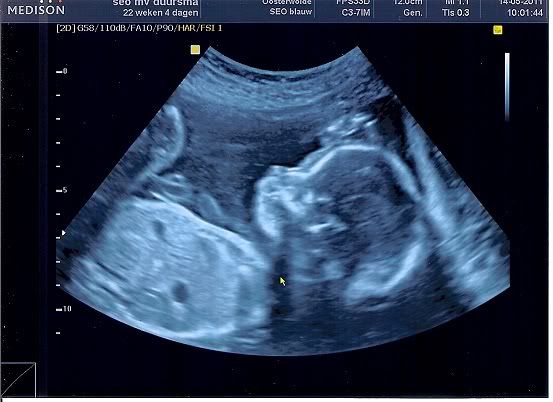

Afgelopen zaterdag hebben we eindelijk onze 20 weken echo gehad! En we zijn erg opgelucht en ontzettend blij, want alles was goed met onze kleine!! De echoscopiste was ontzettend leuk. We kregen zelfs een 3D echo erbij! En ze heeft een paar leuke foto's voor ons afgedrukt op echt fotopapier. We kregen zelfs een sleutelhanger met een klein 3D fotootje erin mee. Wat een ontzettend lief gebaar.

De echo's: